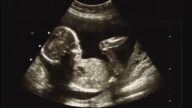

大坂直美宣布怀孕喜讯 将暂别网坛预计2024年复出

日本网球名将大坂直美(Naomi Osaka)今天在社群媒体上传一张胎儿超音波照片,宣布她已怀有身孕...